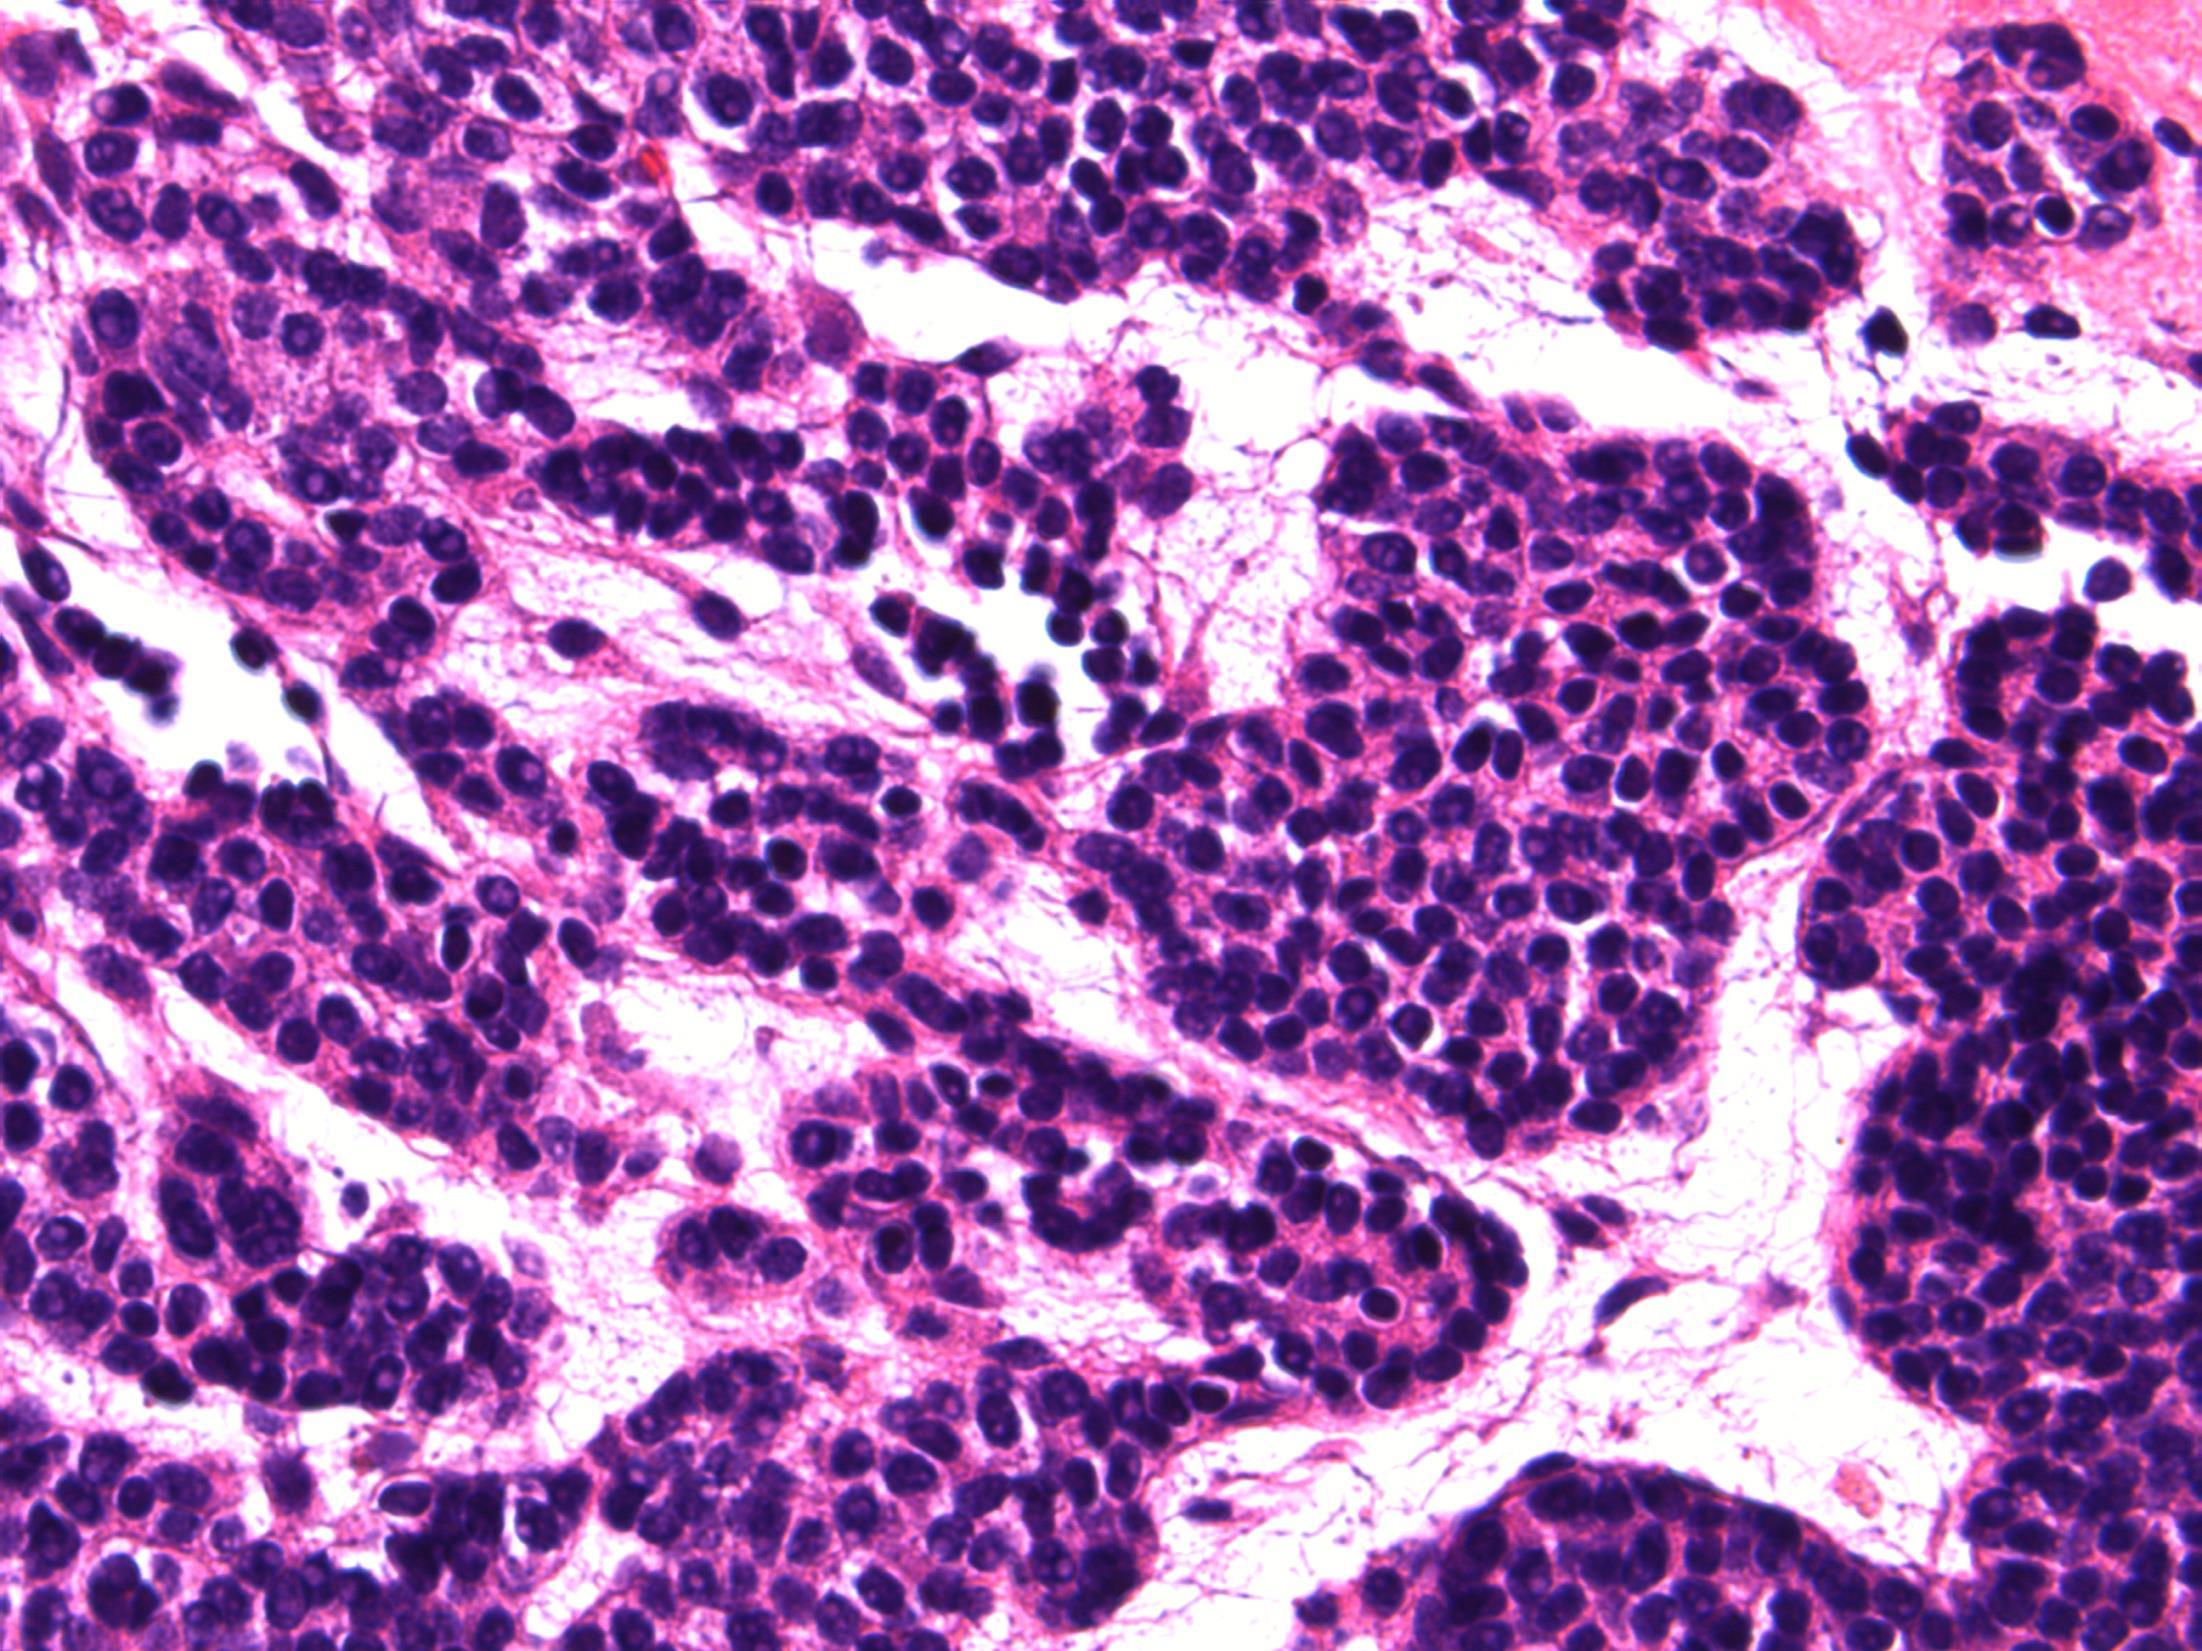

G3 (high-grade) TCC with small cell carcinoma component

Description: Biphasic malignant tumour. High grade large epithelial cell component and high grade small round blue cell tumour component. CIS also seen.

Favoured Diagnosis: G3 (high-grade) TCC with small cell carcinoma component. Plan: Correlate with urine cytology/ previous biopsies. IHC: TCC= AE1/3+, p63+, small cell ca = AE1/3 dot +, CD56+, synapto +. Look for invasion into lamina propria and muscle (staging).

Comments: • Small cell carcinoma is frequently admixed with TCC, SCC or adenocarcinoma of bladder • >90% muscle invasive and metastases common, poor prognosis. • Responds to chemotherapy (cisplatin based) • Differential Diagnosis of pure small cell carcinoma: – Poorly-differentiated urothelial carcinoma – Metastatic small cell carcinoma from other site eg lung – Lymphoma – Alveolar rhabdomyosarcoma – Inflammation (in a crushed, cauterised, superficial or scant specimen)